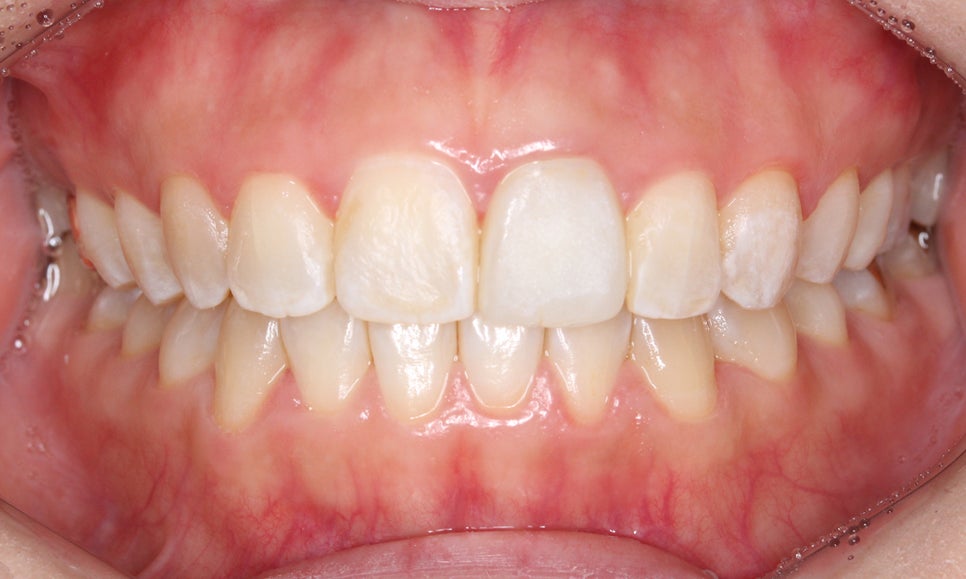

양악교정 후 구내 사진입니다.

한눈에 봐도 전체적인 치아 배열이

가지런해진 모습인데요,

특히 문제가 되었던 송곳니의

덧니 증상도 고르게 교정된 모습입니다.

overbite 사진에서도 과개교합이나

절단교합 증상이 나타나지 않고

바르게 교합되는 모습인데요,

측면에서 본 overjet 사진도

상악의 돌출감 없이 전치부가 교정된 모습입니다.

또한 송곳니와 돌출된 중절치로 인해 상대적으로

설측으로 들어간 느낌이 있던 측절치 또한

바른 위치로 돌아온 모습입니다.